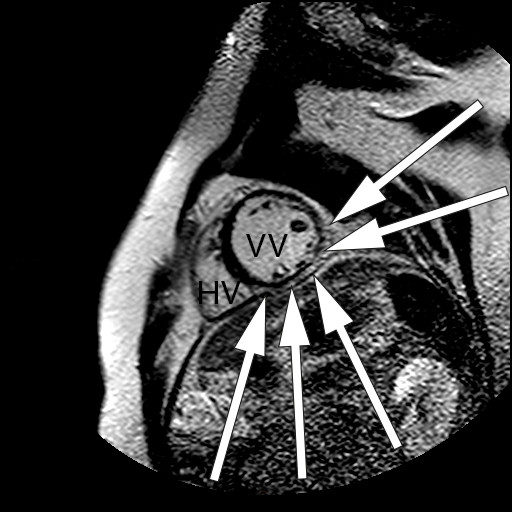

Som ved alle andre undersøkelser er sensitivitet og spesifisitet avhengig av sykdommens prevalens, undersøkelsesmetode og legen som vurderer resultatet av undersøkelsen. Ved MR cor kan man oppdage både inflammatoriske og fibrotiske forandringer som er assosiert med kardial sarkoidose (fig 1–3) (7).

Den aktive, inflammatoriske sykdomsfasen kjennetegnes av økt gadoliniumkontrastopptak ved tidlig undersøkelse og veggfortykkelse som oppstår sekundært til granulomatøs infiltrasjon og ødem (6, 7). Dersom pasientene har utviklet fibrotiske forandringer, vil MR-undersøkelsen vise kontrastopptak ved sen undersøkelse, kalt sen kontrastutvasking (4). Fibrotiske forandringer ved MR-undersøkelse kan være en prognostisk markør som er assosiert med ventrikulære arytmier og mortalitet (4). Fibrosen forekommer som regel ikke i klassiske arterielle forsyningsområder, i motsetning til ved aterosklerotisk hjertesykdom (5). I tillegg vil kontrastoppladningen ved et hjerteinfarkt alltid involvere subendokard (med varierende grad av transmuralitet), mens ved kardial sarkoidose kan kontrastoppladningen forekomme i alle deler av myokard (6).